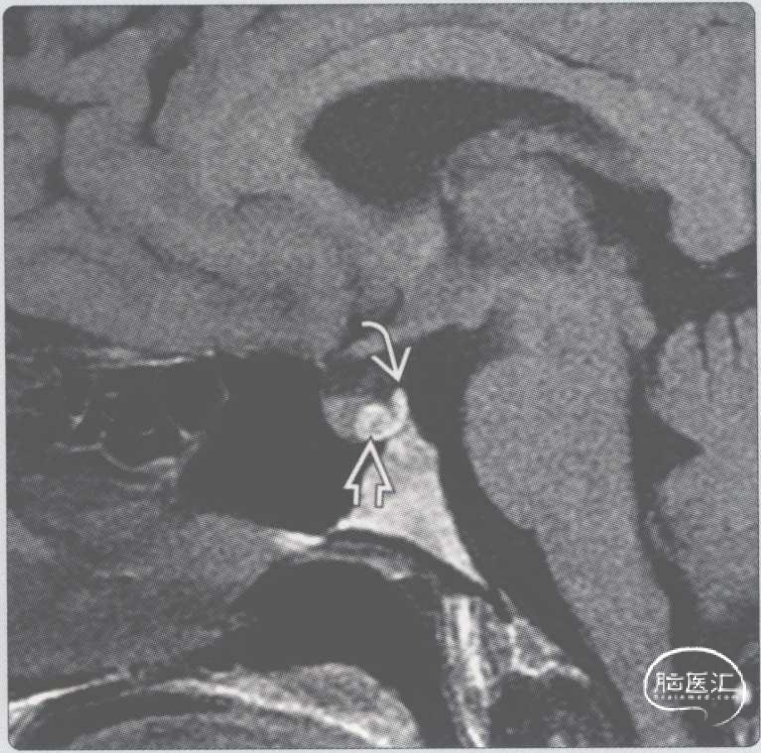

【影像时间·275】一位32岁闭经女性患者